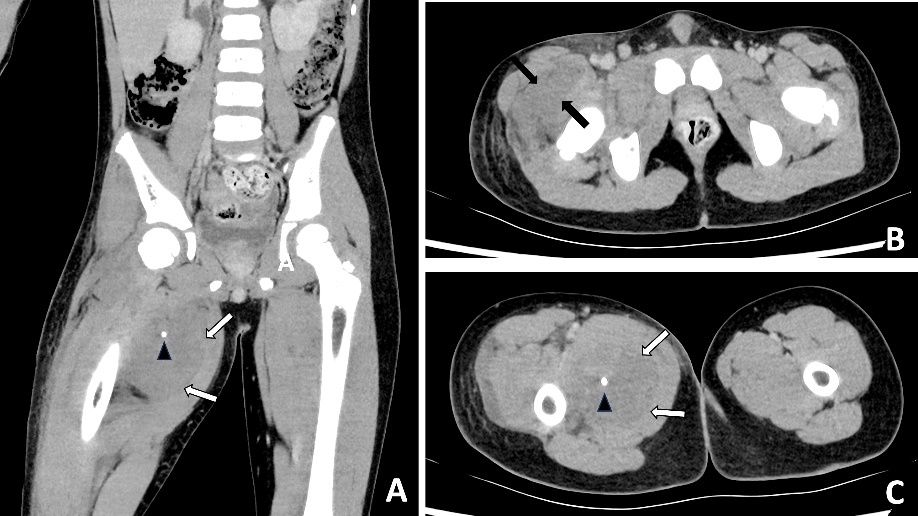

A subsequent washout was performed on day three; intraoperative findings were similar to the first operation. The patient’s fever subsequently settled. An MRI was performed on day 11 to evaluate for possible VM or sarcoma. An MRI revealed a ‘trans-spatial right paraspinal mass involving the trapezius and rhomboid muscles with internal phleboliths, no fluid levels or flow voids, in keeping with a slow flow vascular malformation’ (Figure 4).

In retrospect, the presence of intramuscular phleboliths on CT in the cases presented above was the best clue to the diagnosis of an infected VM. Phleboliths occur in approximately 30 per cent of VMs.15 Intramuscular phleboliths have a limited imaging differential diagnosis and are generally taken to be pathognomic of VM.16 Radiologist and clinician awareness of this rare presentation of VMs is important; if intramuscular phleboliths are identified, the diagnosis of VM should be raised and the use of MRI may further assist in the diagnosis. If clinical doubt remains in an acutely unwell patient, prompt surgery to exclude necrotising soft tissue infection is prudent.

Timely surgical exploration is indicated in septic patients where necrotising soft tissue infection cannot be excluded. However, it is important to consider rare conditions that may present similarly, such as infected VMs. The presence of intramuscular phleboliths on CT, especially in a child, is the best imaging clue to this unusual diagnosis and should not be overlooked.